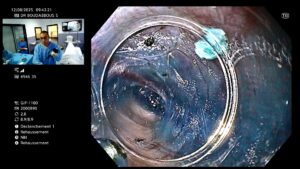

- Le tunnel est refermé avec des clips endoscopiques.

🏥 Hospitalisation : 1 à 2 jours